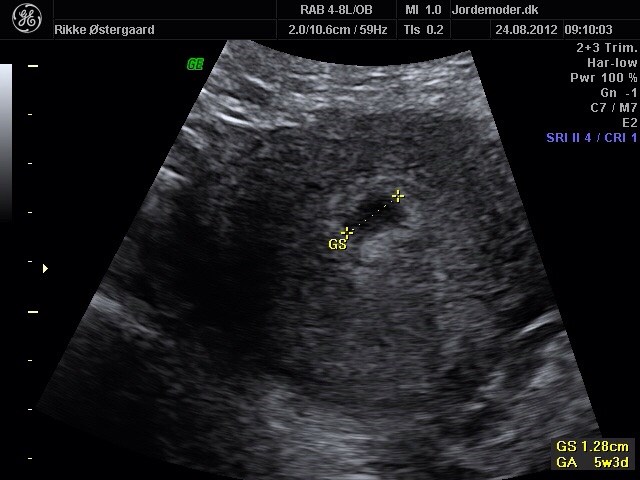

Hvor langt er du i forhold til sidste mens? Eller andre pejlemærker? Gravid er du i hvert fald, om fosteret bliver hvor det skal kan ingen give dig garantier for hverken scanninger eller test.

Men når du har set hjerteblink er der er en stor sandsynlighed for en sund og rask graviditet, men du kan ikke være sikker på hjerteblink før du er i uge 7+ så der er jo lige nogen uger til